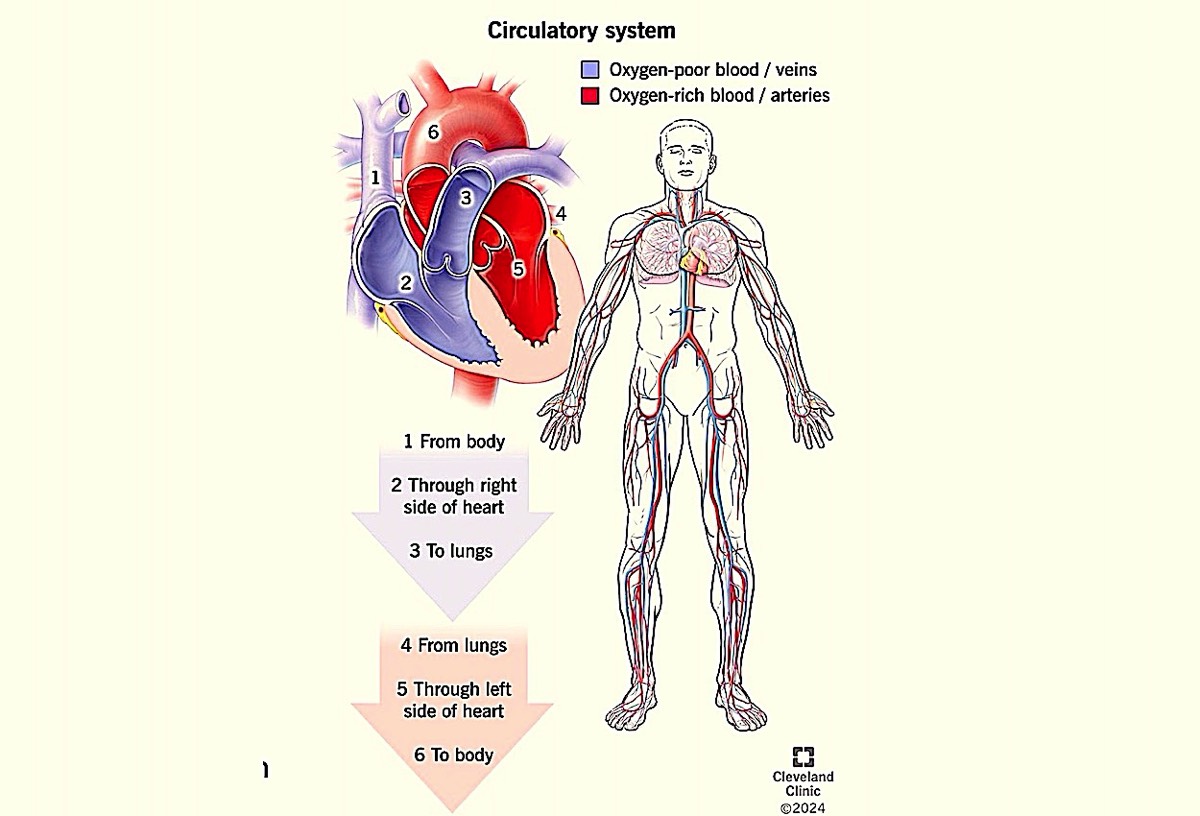

The heart is a muscular organ that is situated in the front of the chest. It pumps blood all through the body in a process called circulation. Apart from the heart, the blood vessels and blood as a unit constitute the cardiovascular system.

Your circulatory system, or cardiovascular system, supplies oxygen and nutrients to your whole body and removes waste through your blood. Your heart pumps blood that flows through your arteries, veins and capillaries. These blood vessels and your heart form your circulatory system. They work together to ensure your cells have what they need.

my.clevelandclinic.org